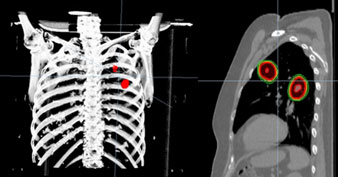

| Пример стереотаксической лучевой терапии метастатических поражений в левом легком. Лечение проводилось с синхронизацией дыхательного цикла под визуальным контролем низкодозового КТ. |